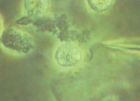

常染色體1.尿卟啉原合成酶部分缺乏即卟膽原脫氨酶缺陷引起。患者的此酶活性大約只有正常人的50%。

3.卟膽原脫氨酶至少有3種不同的同工酶已知一種存在於所有組織中,另一種只存在於紅細胞中但缺陷雖然在這些組織和紅細胞存在,但其功能上的表現似乎僅限於肝臟。

肝細胞本病為常染色體顯性遺傳位於11號染色體11q24上卟膽原脫氨酶等位基因發生突變,患者肝細胞、淋巴、皮膚、上皮羊膜及紅細胞內卟膽原脫氨酶活性僅為正常人50%致使卟膽原轉為尿卟啉原途徑受阻,同時由於ALA合成活性增強表現卟膽原和ALA在體內蓄積研究報導這種基因突變至少有4種類型,因而酶活性表現不一有些酶的免疫活性及催化生物活性減低有些免疫活性正常,催化活性減低。此外,因有的患者紅細胞內酶活性正常,而其他組織內減低。證明很可能控制酶表達的不止1個等位基因,控制紅細胞為1個基因,控制其他組織內酶表達的為另1個基因。